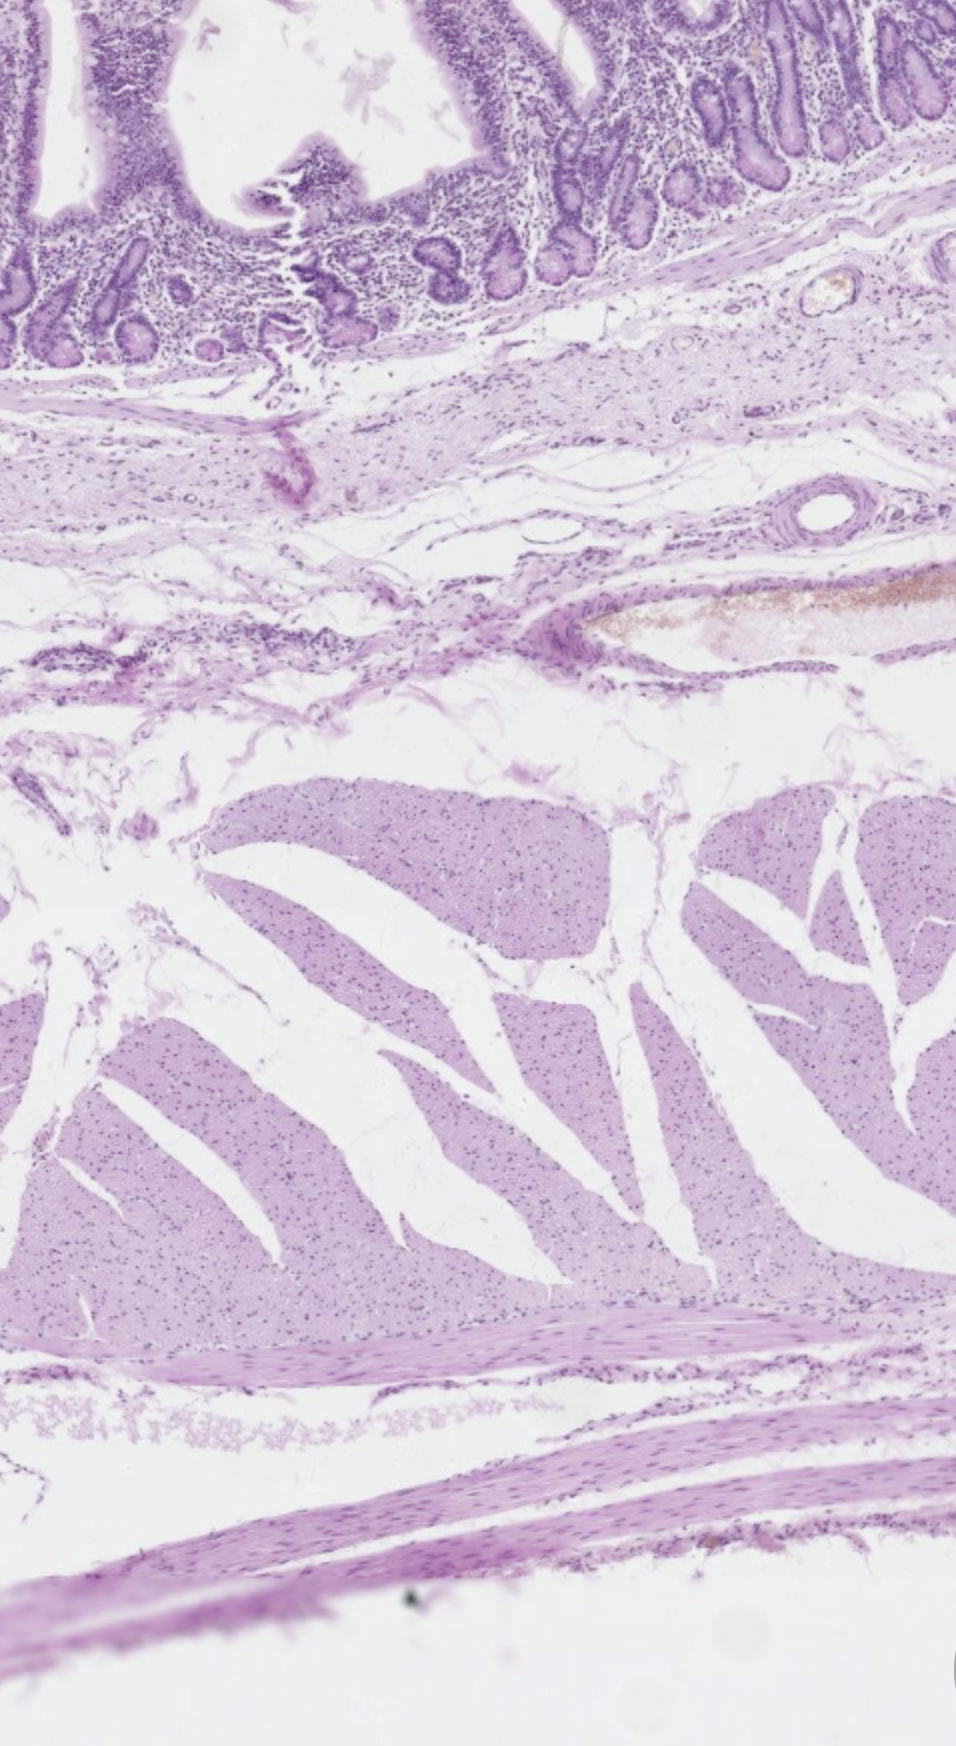

Je kijkt naar het jejenum van een paard. Wat wordt hier aangegeven?

A

Gladde spierweefsel vezels in de lamina muscularis mucosa

Gladde spierweefsel vezels in de lamina muscularis circularis

Gladde spierweefsel vezels in de lamina muscularis longitudinis

Is dit een longitudinale of transversale doorsnede van het jejenum?

Longitudinale doorsnede (parallel aan de vezels in de lamina muscularis longitudinalis, die je kan zien als strepen)